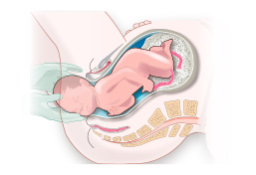

En el noveno mes de gestación, el cuerpo de la embarazada se prepara para el parto. El bebé ya se habrá encajado y es probable que la tripa, ya muy voluminosa, se note más baja. Algunas mujeres días antes de dar a luz expulsan el tapón mucoso. Cómo es una embarazada de 9 meses En el...